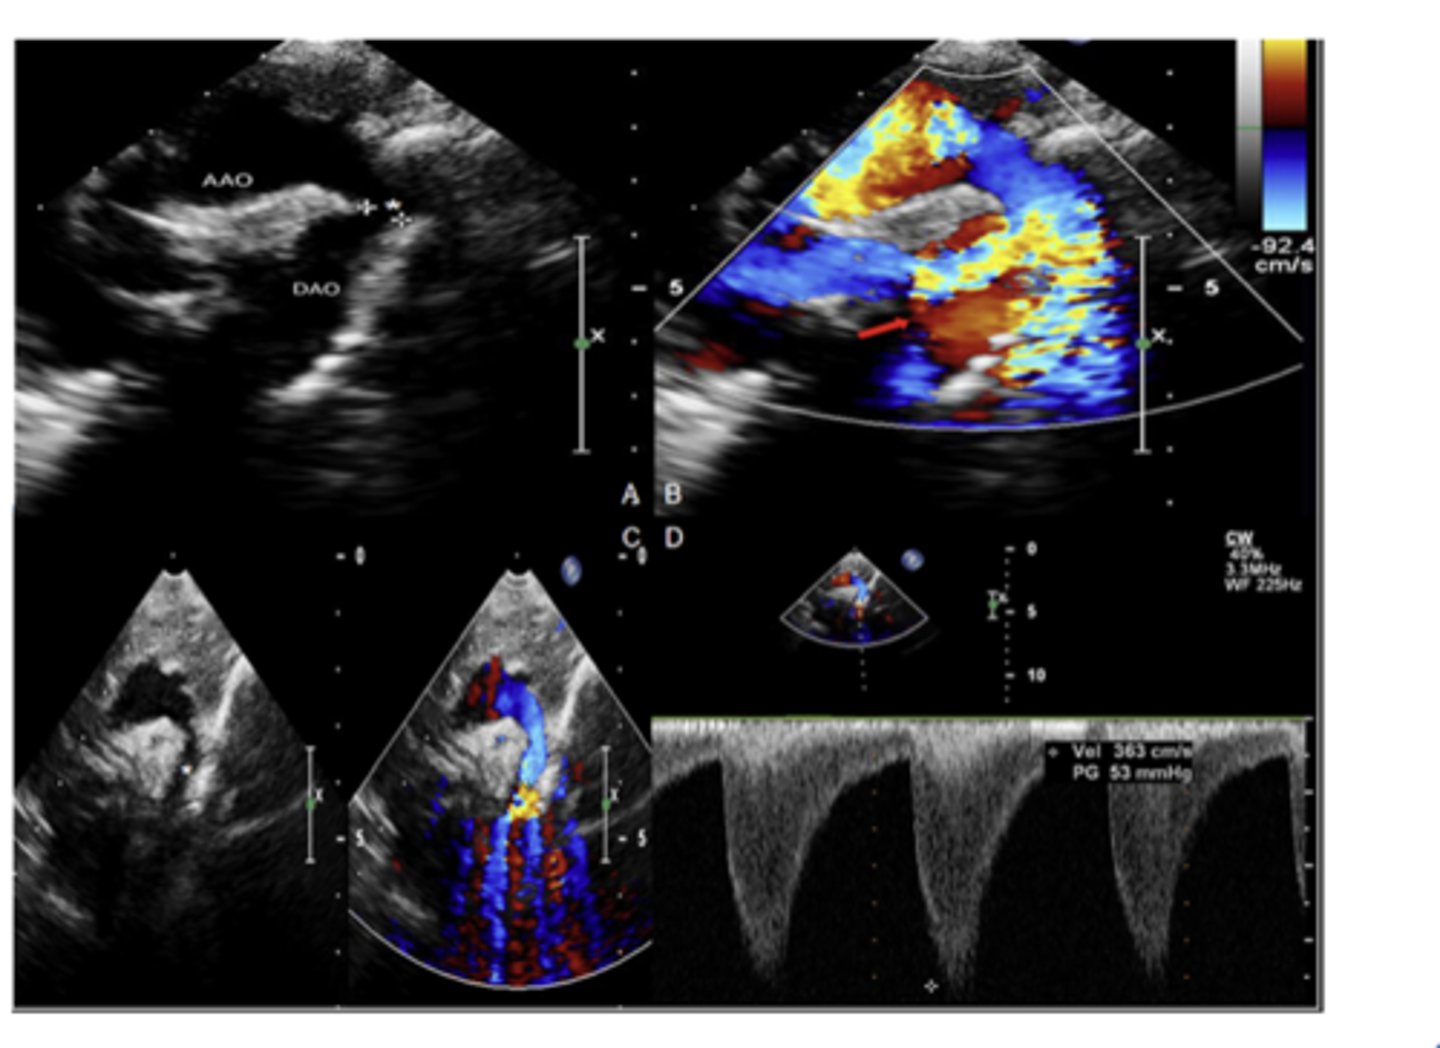

severe COA

WHAT LESION?

COA